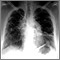

Lung cancer - frontal chest x-ray

Bronchial cancer - chest x-ray